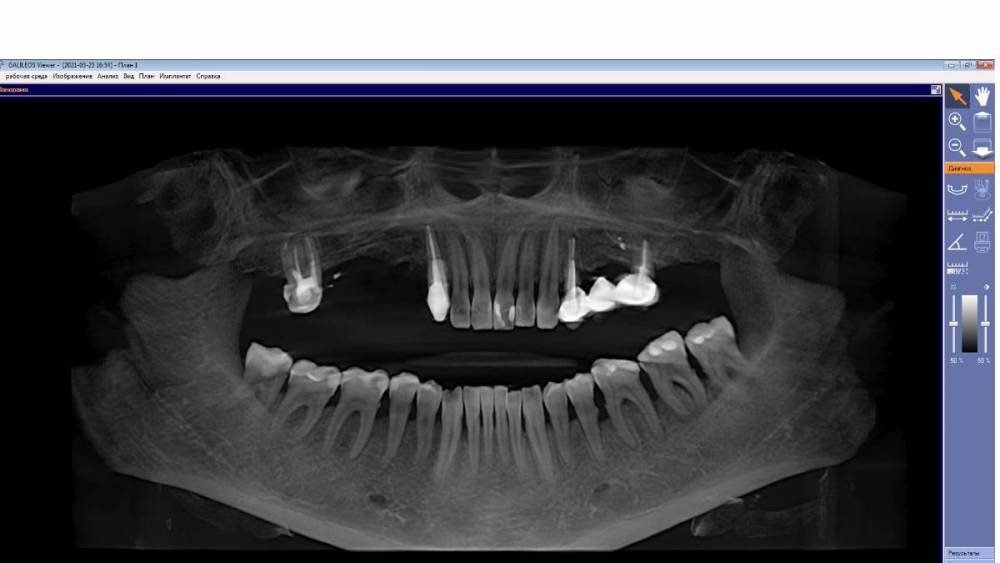

YnA Опубликовано 28 июня, 2021 Поделиться Опубликовано 28 июня, 2021 Добрый день! Хочу сохранить как можно больше зубов. Но 3 хирурга, у которых консультировалась сказали удалять кучу зубов((( Посмотрите, пожалуйста, Кт, дайте оценку. https://disk.yandex.ru/d/0rv54TX9XGxvwQ Ссылка на комментарий

YnA Опубликовано 29 июня, 2021 Автор Поделиться Опубликовано 29 июня, 2021 wladdX, спасибо, что не прошли мимо! А конкретно что нужно удалить? Мне говорят 13,17,24,26. Ставить 7 имплантов. А на 17 и 26 есть воспаление? Можно ли делать синус лифтинг вместе с имплантами? Ссылка на комментарий

wladdX Опубликовано 29 июня, 2021 Поделиться Опубликовано 29 июня, 2021 Именно 13,17,24,26. Да, в области корней зубов 17 и 26 есть хронический воспалительный процесс. Да, во многих случаях возможно проведение имплантации при синус-лифтинге. В любом случае, принимать решение будет оперирующий Вас хирург. 1 Ссылка на комментарий